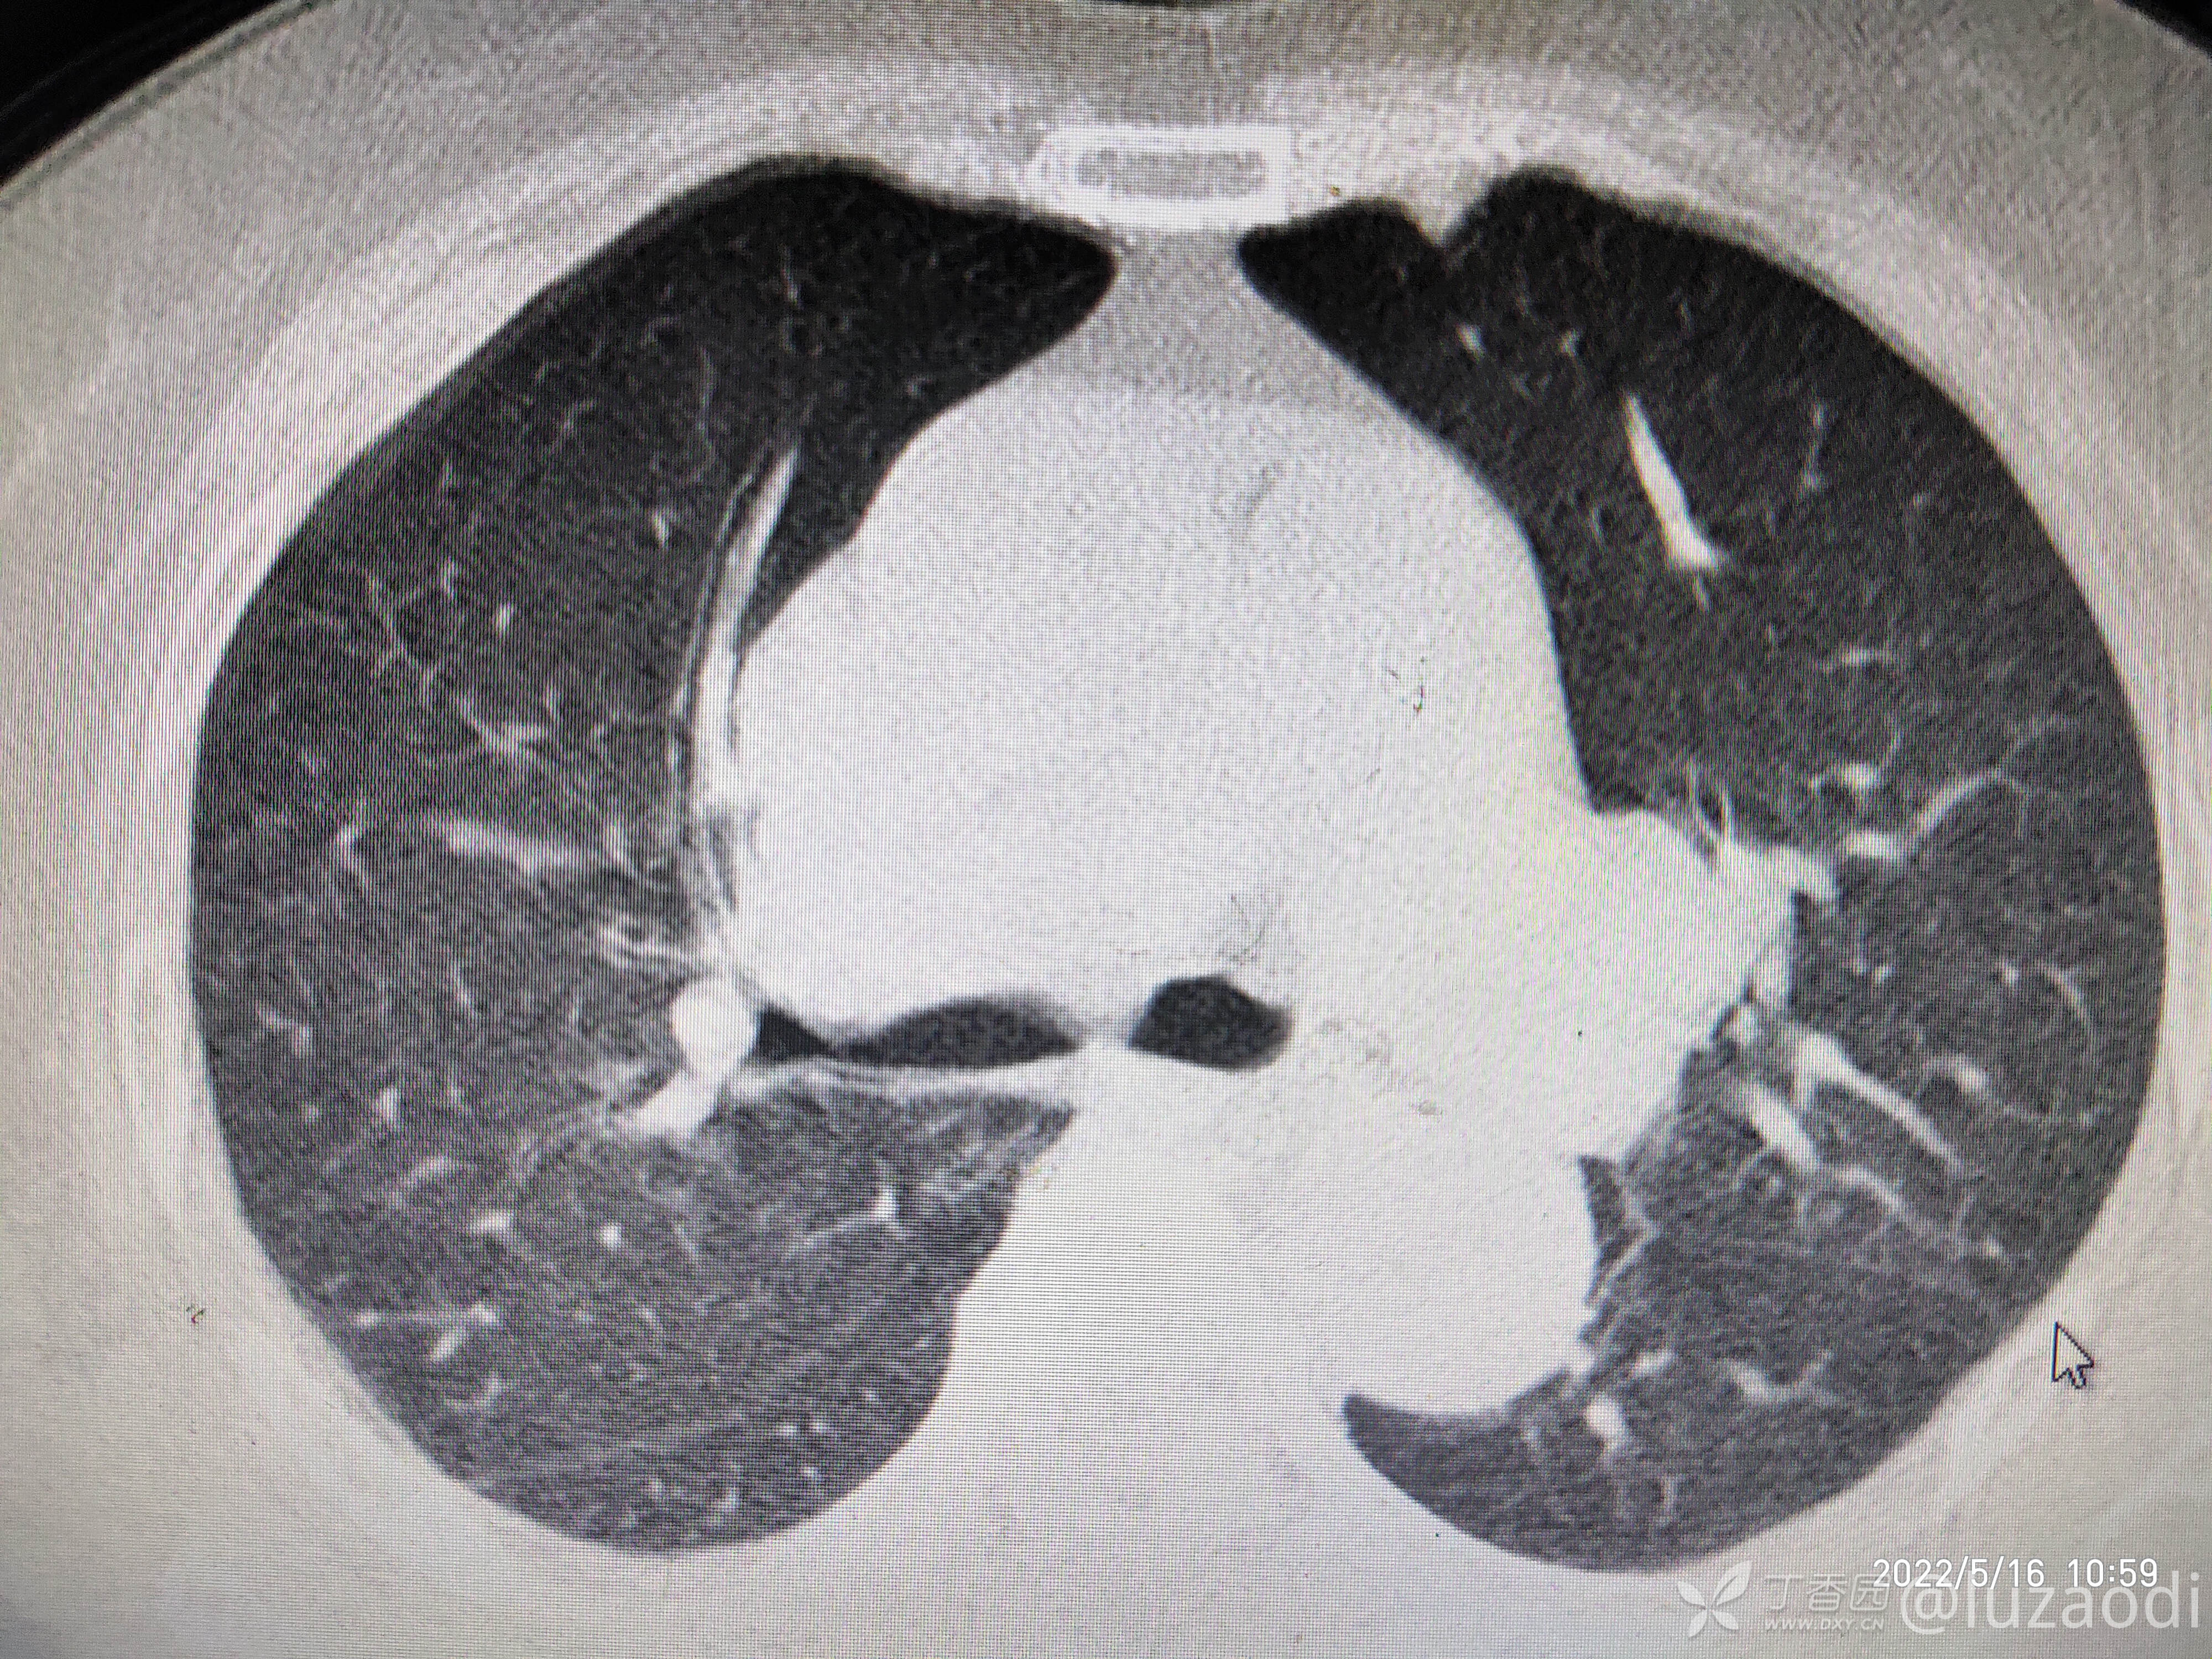

治疗经过:入院后患者仅有乏力,未见明显神经定位征。近期无发热、咳嗽、腹泻症状。遂予血糖、心电图、生化检查及影像检查,结果如下:

我去。。。。。视频只能上传一个,头颅CT上传不了,我直接说报告吧。头颅CT报腔隙性脑梗。